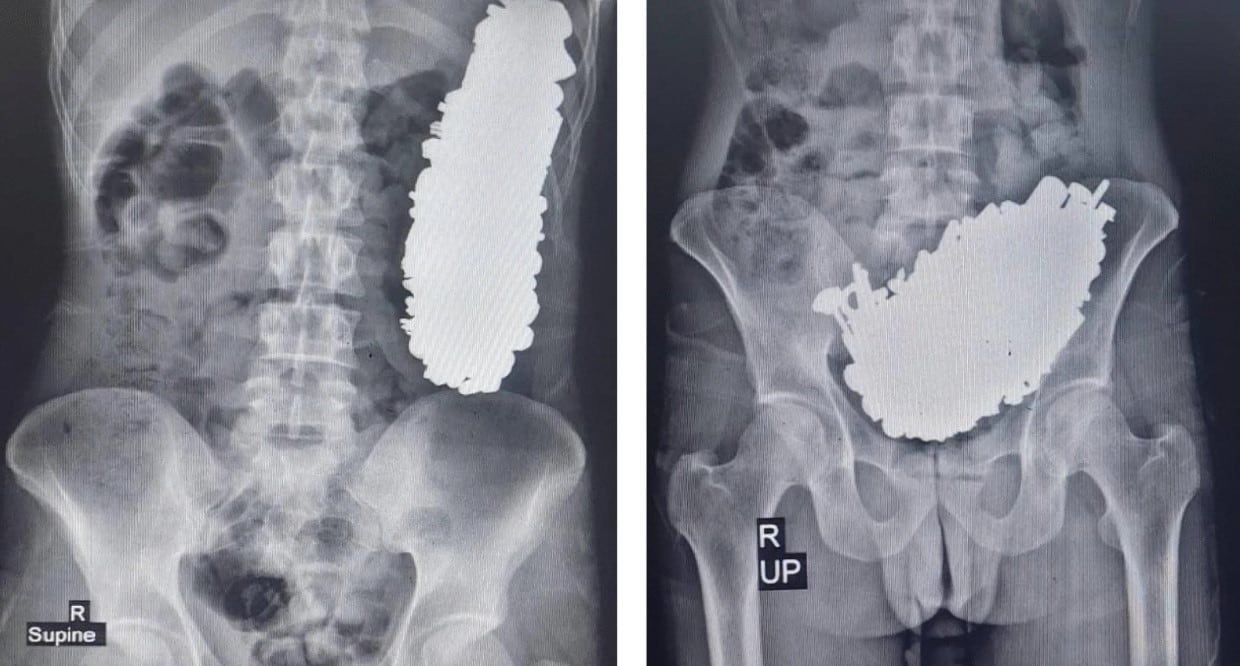

Un equipo de médicos del Hospital Imam Khomeini, en Ahvaz, Irán, informó esta semana sobre la extracción de 452 objetos metálicos del cuerpo de un hombre de 36 años. El caso fue publicado en la Journal of Medical Case Reports. Según el informe, el paciente llegó al hospital con síntomas de dolor abdominal crónico, vómitos frecuentes e intolerancia a líquidos y alimentos.

Los familiares del hombre mencionaron que, tres meses antes de su ingreso, él había ingerido objetos metálicos. Tras realizarle exámenes de radiografía y endoscopia, los médicos detectaron múltiples piezas metálicas que bloqueaban su estómago.

A pesar de la gravedad, el paciente estaba consciente y sus signos vitales se mantenían estables. En total, se extrajeron 452 objetos, incluyendo tornillos, tuercas, llaves y piedras, con un peso de 2,9 kilos.